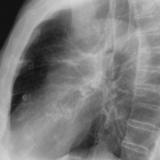

Ao valve calcif (lat only)

Date: 01/26/2009

Views: 2739